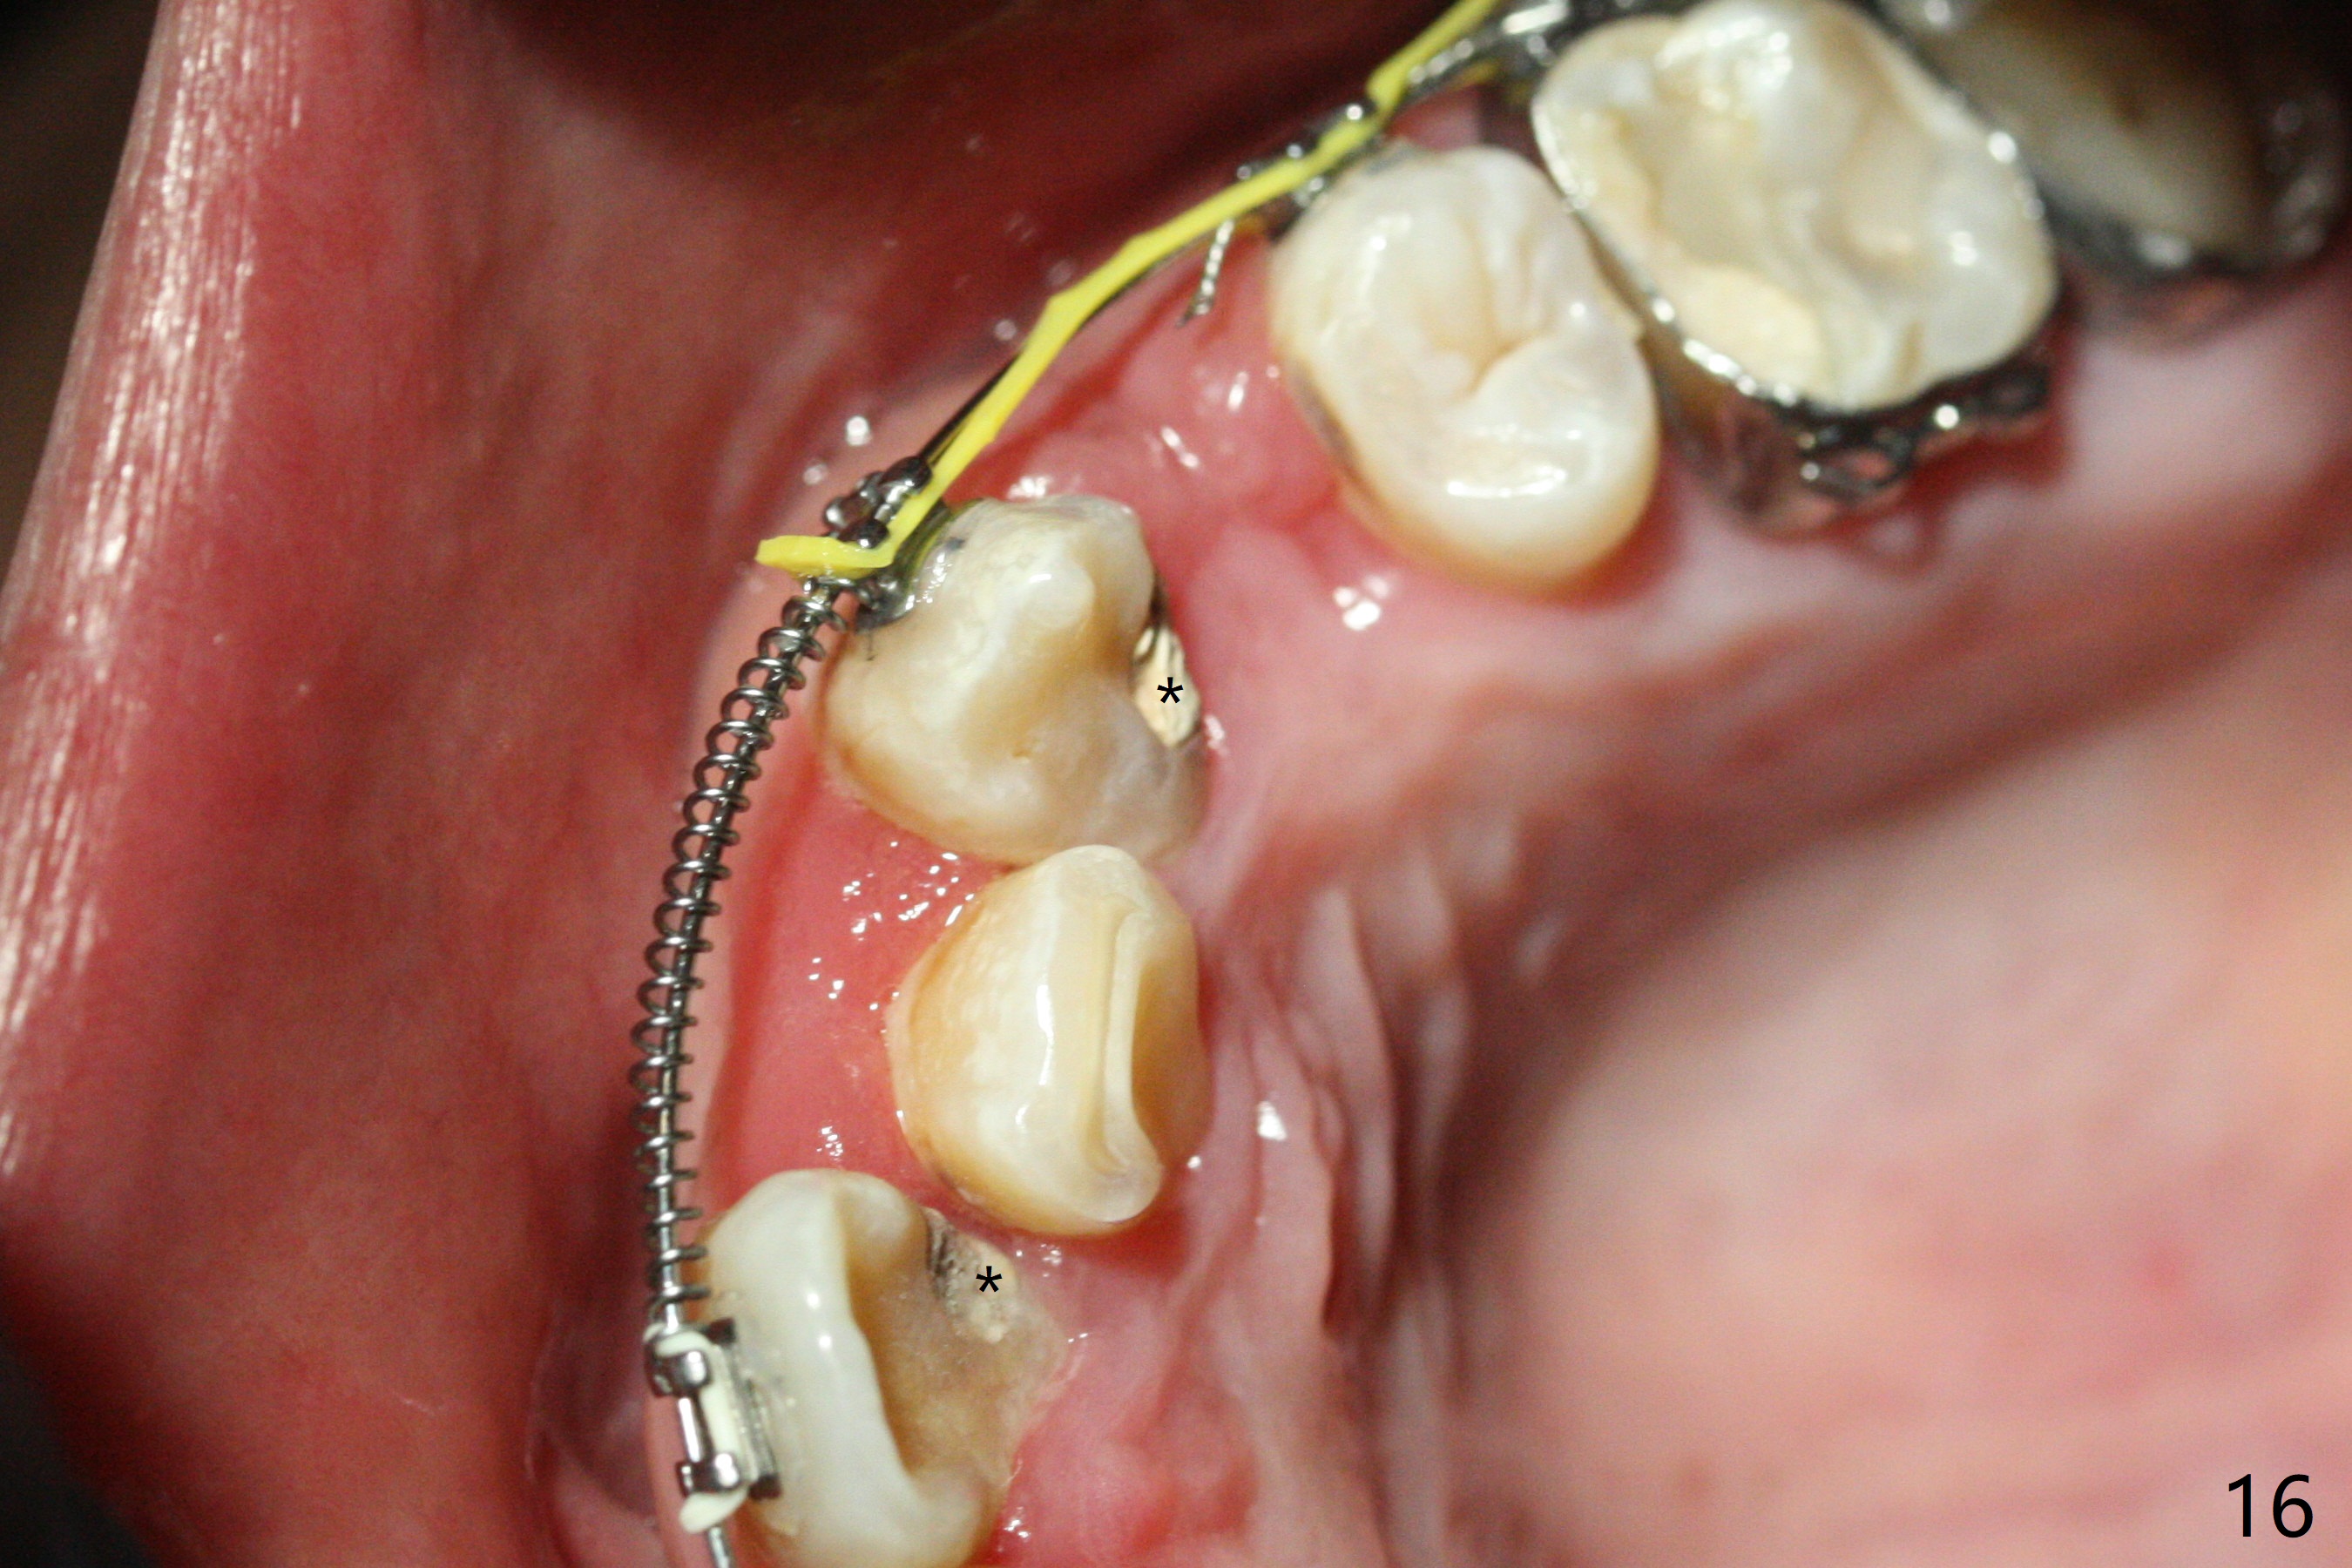

Severe crowding (Fig.1-7) appears to be alleviated especially 2 months after UR5 extraction. Diastemata seem to form mesial and distal to UR2 (Fig.8). Because of severe wear at UR3 (Fig.6), there is no bracket placement differential around it (Fig.8 (14 niti wire)). Lower bands and brackets are placed a week later (Fig.9-11). Because of tight space between LR4 and the opposing tooth (Fig.10), band adhesive is applied to L7 occlusal surface to open the bite (Fig.9). There is an abrupt kink of 12 niti wire between LL4 and 6 (Fig.11). The latter does not improve much in a month; the wires remain the same (Fig.12). For LL2, LR4 has been retracted for ~ 1 month (Fig.13). There is mild tension when 18 ss wire is inserted between LL4 and 6 five point five months post banding (Fig.14). UR4 has been distalized for a month using buccal power chains x3 resulting in rotation; to counter the rotation, a lingual button is placed with power chain x3 lingual and x2 buccal (Fig.15). With space gaining, it is time to finish definitive filling (Fig.16 *). Next visit check midlines, overjet, interdigitation, and molar classification. R4s distalize, but associate with rotation because of power chains buccal and lingual 8 months post banding (Fig.17,18). With the use of the same wires, power chains are applied lingual to continue distalization and rotation correction (Fig.20,21). Lingual buttons are placed at L2s buccalization (Fig.19) and mesialization (Fig.22,23). It appears that space should be created distal to LR3. That is that the lower anterior teeth should be shifted to the right, although it may be not appropriate for the midline.